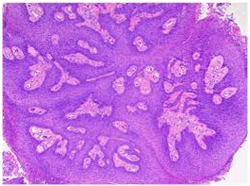

Histopathological statutes: The squamous epithelium displays finger like projections, the epithelial maturation pattern is orderly with epithelial hyperkeratosis. Spinous epithelial cells may depict cytoplasmic vacuolation with pale, clear perinuclear haloes, nuclear pyknosis and infrequent basilar hyperplasia. Oral squamous papillomas frequently display koilocytosis on account of the co-existent cytopathic influence. Atypical nuclear alterations may be exemplified; particularly with immune-compromised (HIV positive) individuals.9 The epithelium displays a typical maturation pattern with prominent hyperkeratosis. Epithelial to basal cell quantification is moderate (basilar hyperplasia) along with an extensive koilocytic transition.1 Virally induced carcinomas are the poorly differentiated, non-keratinizing tumours and may be enunciated in the tonsils of sexually active young men. Majority of the tumours elucidate the p16 proteins. Oro-pharyngeal cancers which are reactive for human papilloma virus (HPV) frequently depict basaloid morphology. Apart from a viral genesis, squamous papillomas may ensue from mechanical irritation or may be genetically determined as a constituent of Cowden’s syndrome.

Figure 8 Multiple papillomas-pharynx

Figure 9 Squamous epithelium lined Papillomas-Uvula.